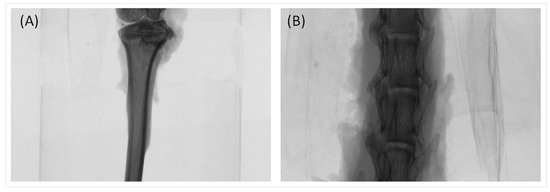

2.3. Trabecular Bone Analysis (Spine)

| Spine | I-OVX | I-0.05PRP | I-0.5PRP | I-0.05PRP/L | I-0.5PRP/L | S-OVX | S-0.5PRP | S-0.05PRP/L | S-0.5PRP/L |

|---|---|---|---|---|---|---|---|---|---|

| BV/TV, % | 30.51 (1.90) | 26.13 (1.29) | 27.60 (1.18) | 35.93 a (1.35) | 32.00 (1.31) | 31.93 (2.79) | 34.73 (1.95) | 30.61 (2.51) | 31.57 (2.37) |

| TbTh, mm | 0.16 (0.01) | 0.14 (0.00) | 0.14 (0.00) | 0.18 b (0.01) | 0.17 (0.00) | 0.18 (0.01) | 0.17 (0.01) | 0.16 (0.01) | 0.16 (0.01) |

| TbN, mm−1 | 1.92 (0.11) | 1.84 (0.08) | 1.93 (0.07) | 2.01 (0.07) | 1.94 (0.08) | 1.81 (0.16) | 2.01 (0.10) | 1.85 (0.08) | 1.93 (0.09) |

| TbSp, mm | 0.33 (0.03) | 0.34 (0.02) | 0.31 (0.01) | 0.29 (0.01) | 0.32 (0.02) | 0.32 (0.03) | 0.31 (0.01) | 0.31 (0.01) | 0.31 (0.02) |